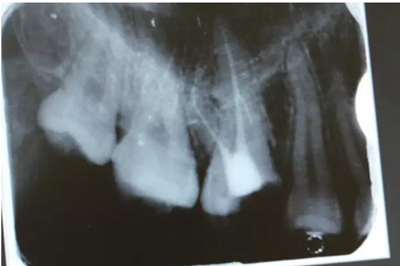

病例一 女性,20歲,大學(xué)生,要求補(bǔ)牙,檢查口內(nèi)可見A6大面積缺損,近中牙齦息肉,拍X片,根管充填物略差,但根周未見明顯陰影,口內(nèi)檢查無(wú)叩痛。建議患者冠延長(zhǎng)手術(shù)+高嵌體修復(fù)。

患牙遠(yuǎn)中邊緣嵴完整,強(qiáng)度沒(méi)有降低,故擬保留遠(yuǎn)中邊緣嵴,高嵌體修復(fù)。首先去除腐質(zhì)及原墊底材料,流體樹脂+3M Z350XT樹脂墊底。局麻下行冠延長(zhǎng)手術(shù)。在此需要提及個(gè)人的一個(gè)觀點(diǎn)。冠延長(zhǎng)手術(shù)原則上要求3-6個(gè)月以上才能永久修復(fù)。但是個(gè)人喜歡后牙肩臺(tái)建立在齦上,所以修復(fù)后的修復(fù)體邊緣位于牙齦上方1mm,對(duì)牙周的愈合影響較?。ㄈ绻麨辇l下邊緣則要慎重),故該患者術(shù)中按照齦上邊緣的設(shè)計(jì)進(jìn)行冠延長(zhǎng)手術(shù)。以下為術(shù)中: